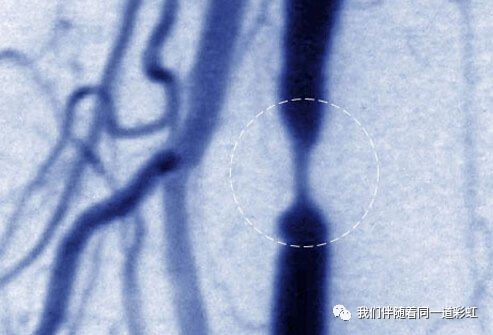

勃起功能障碍背后的机制

当血液充满阴茎的两个腔室(称为海绵体)时,就会发生勃起。这会导致阴茎膨胀和变硬,就像气球一样,因为它充满了水。该过程由来自大脑和生殖器区域的神经冲动触发。任何干扰这些冲动或限制血液流向阴茎的东西都可能导致勃起功能障碍。

如果勃起功能障碍是由通往阴茎的动脉阻塞引起的,则可以使用手术来恢复血流。最佳候选人通常是年轻男性,其阻塞源于胯部或骨盆损伤。不建议全身动脉广泛狭窄的老年男性进行手术。